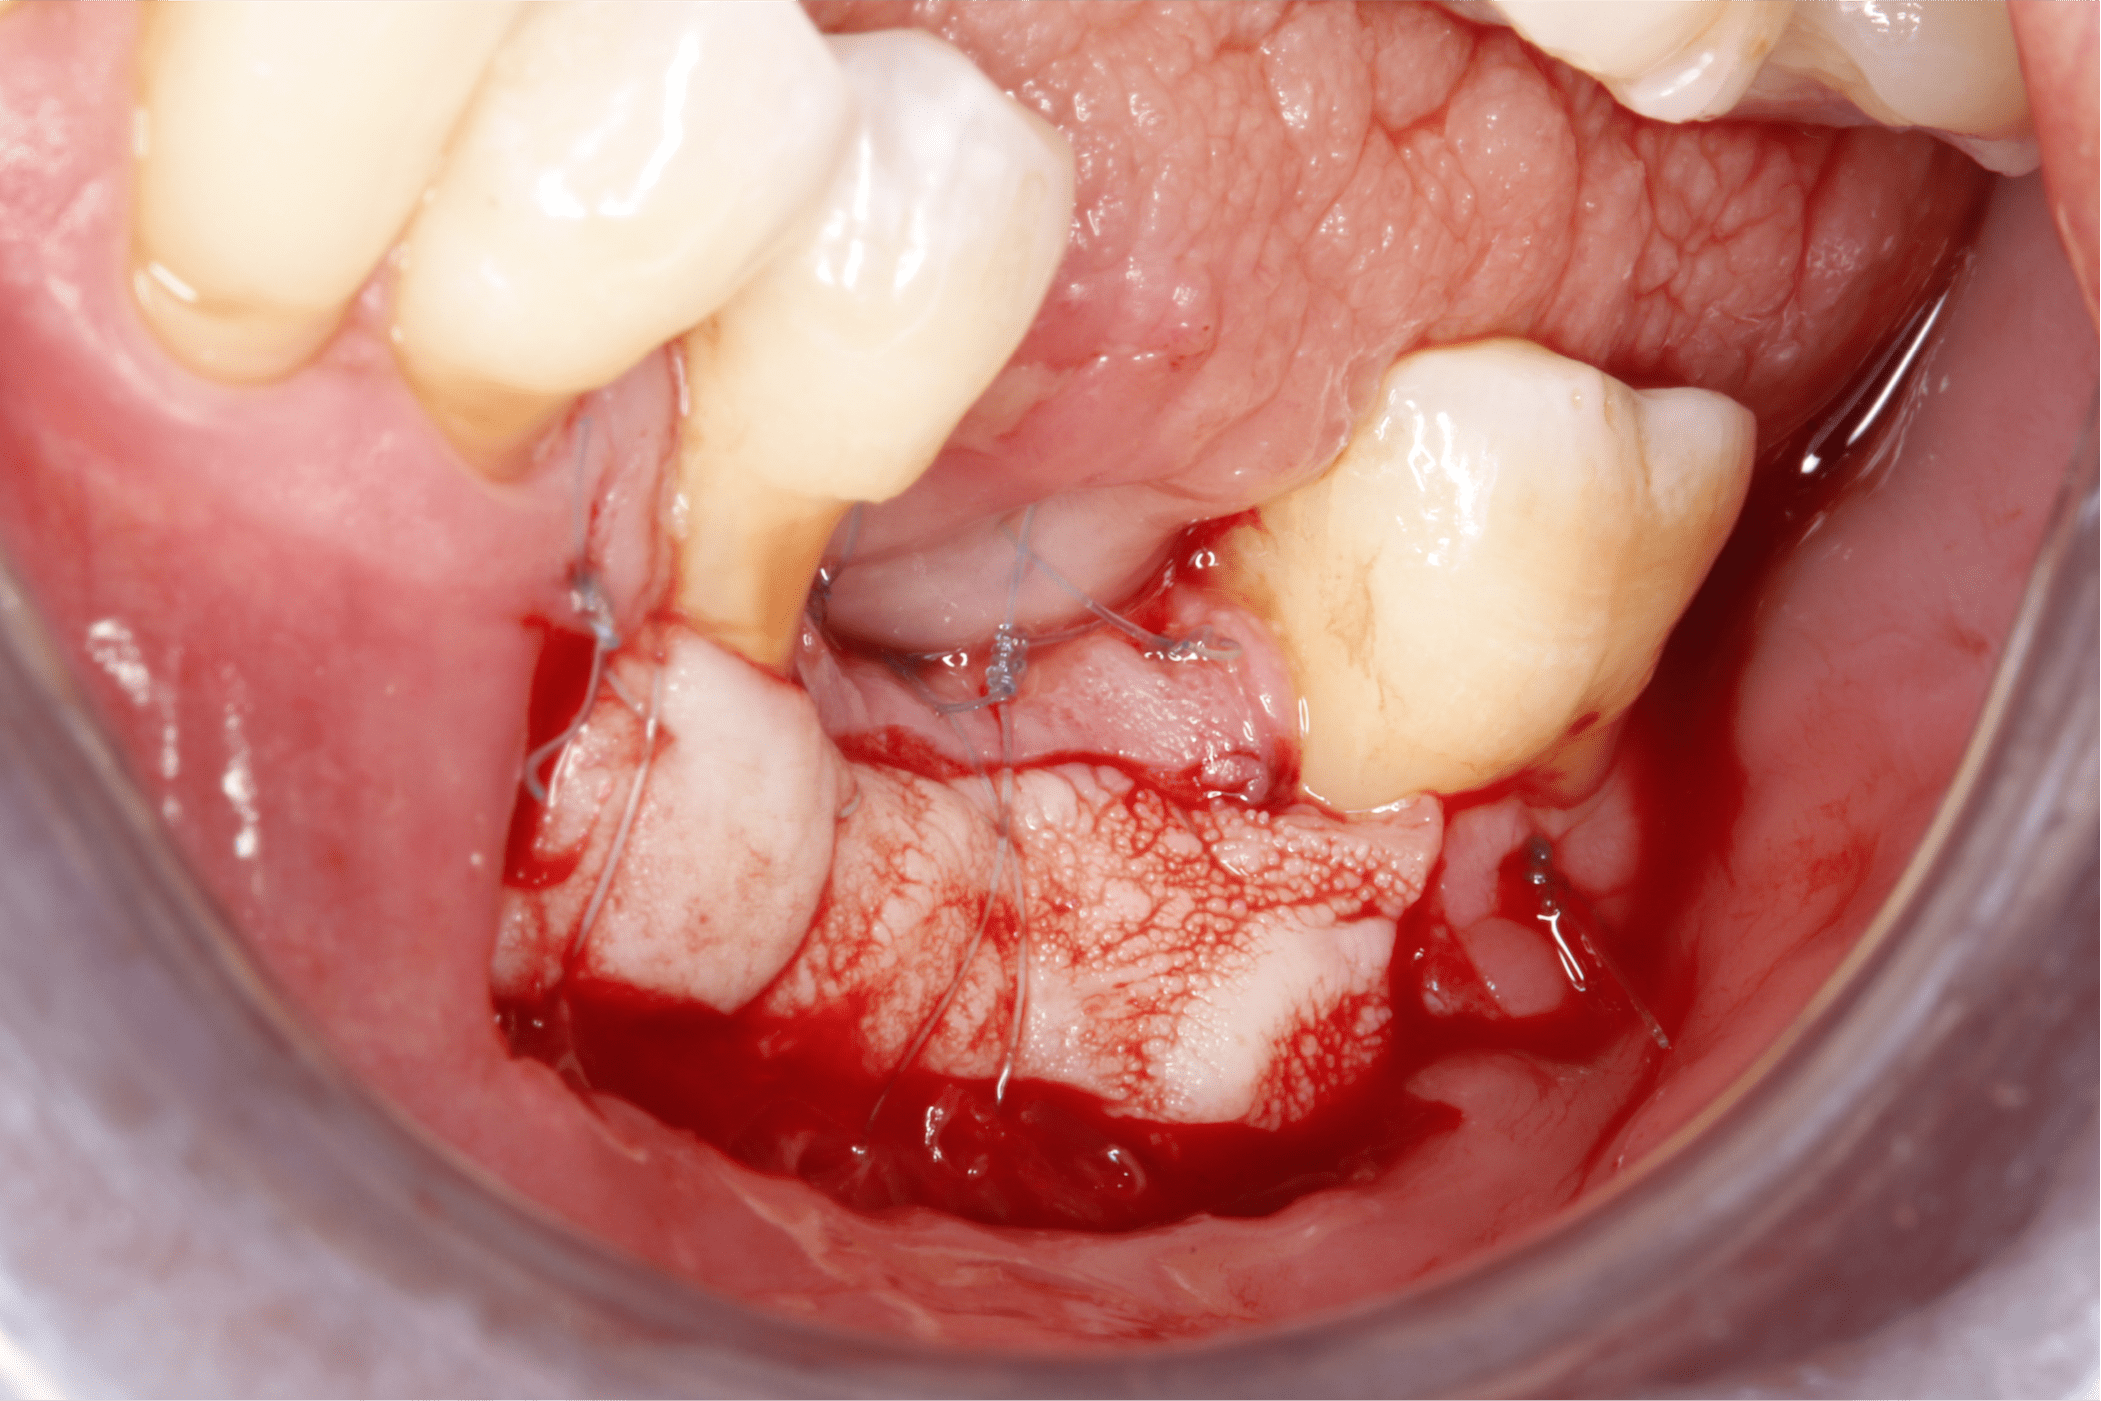

Tras un enjuague antiséptico, se anestesia la zona a tratar y se procede a preparar el lecho receptor por medio de incisiones de espesor parcial dejando periostio expuesto, esto con la intención de darle aporte vascular al injerto. (Fig. 6 y 7).

Fig. 6

Fig. 7